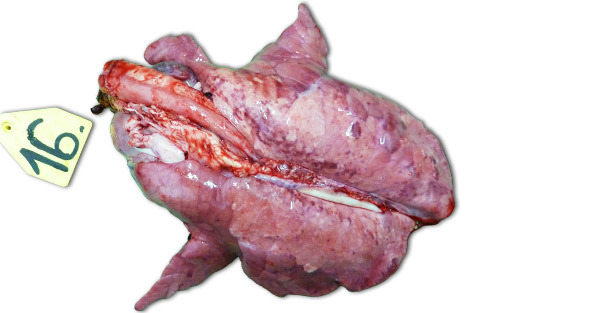

Lors d’infections expérimentales réalisées dans des élevages isolés, les signes cliniques et les lésions observées dépendent beaucoup de la pathogénicité de la souche utilisée pour inoculer les animaux. Les lésions respiratoires les plus sévères sont observées à 7-14 jours PI. Macroscopiquement, il s’agit de zones consolidées, foncées et tachetées qui affectent plus gravement les lobules cranio-ventraux, mais qui peuvent se trouver disséminées dans tout le tissu pulmonaire (photo 1). Les principales lésions histopathologiques comprennent : (1) hypertrophie et hyperplasie pneumocytaires, (2) infiltration mononucléaire septale, (3) débris nécrotiques intra-alvéolaires, (4) accumulation intra-alvéolaire de cellules inflammatoires et (5) accumulation péri-vasculaire de cellules inflammatoires.

Photo 1 : poumons d’un porcelet sacrifié 14 jours PI, inoculé avec une souche à forte pathogénicité de type 1 sous-type 3 « Lena ».".